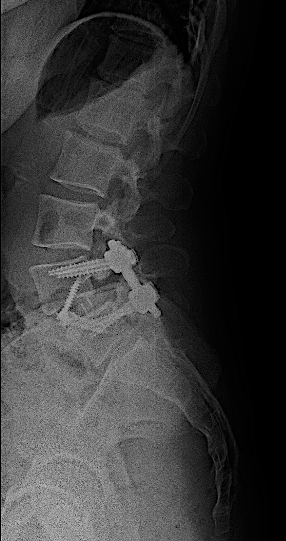

Obsérvese el incremento de la lisis de la pars en las RX dinámicas. La paciente no presentaba clínica radicular significativa por lo que se optó por ALIF L5-L6. El disco L4-L5 presentaba un grado bajo de degeneración.

Tras retirada de faja, la paciente seguía presentando lumbalgia mecánica. Obsérvese la lisie de la pars.